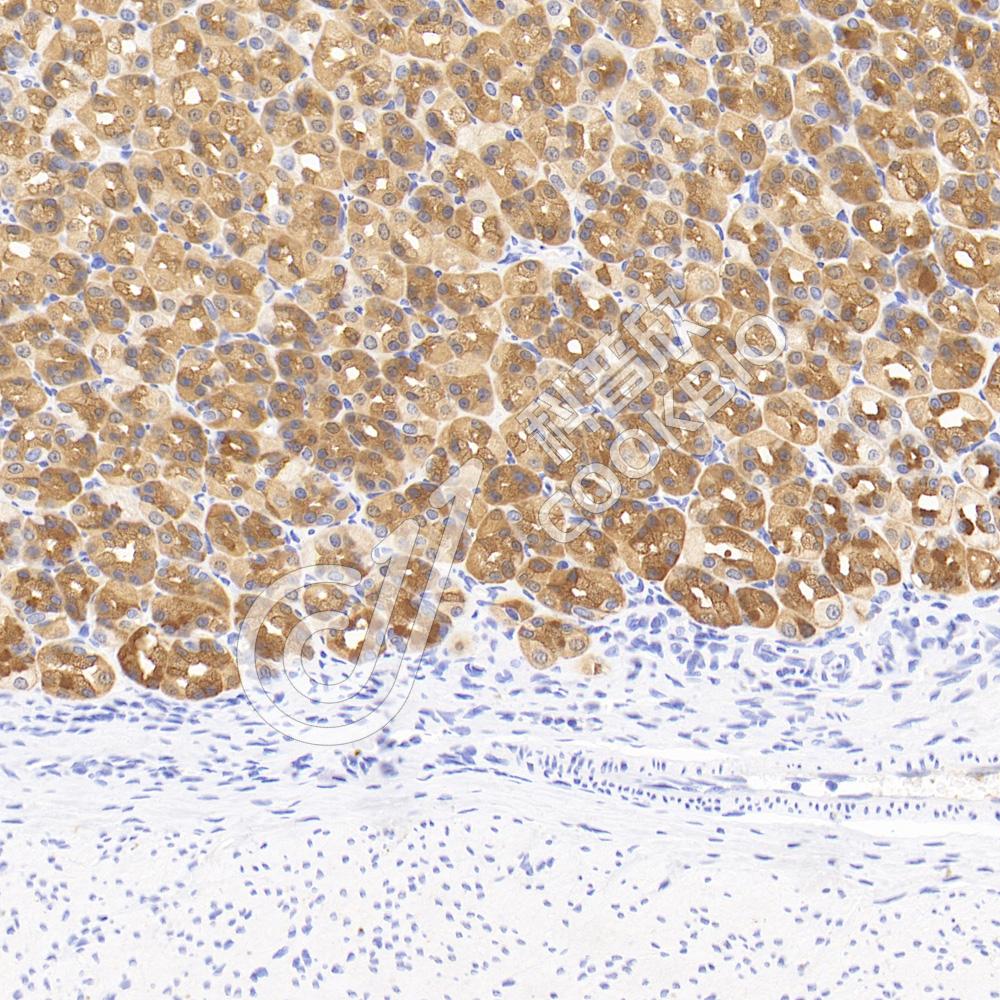

IHC检测Cytokeratin 8蛋白(货号 K133693).

样品: 大鼠胃, 4%多聚甲醛 (货号KSG1101) 固定12-24小时.

抗原修复: 柠檬酸抗原修复液(干粉, pH 6.0) (KSG1201), 98℃, 20分钟.

—抗: 1: 600稀释, 4℃ 孵育过夜.

二抗: S-vision免疫组化多聚二抗(山羊抗兔),即用型 (货号KB3906), 室温孵育20分钟.